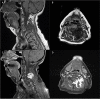

Intramuscular myxomas are rare, benign mesenchymal tumours, occurring predominantly in large skeletal muscles as large, slow-growing and painless masses. Spinal occurrence is rare, and may present incidentally, or diagnosed via localized symptoms secondary to local infiltration of surrounding structures. Differential diagnosis based on imaging includes sarcomas, meningiomas and lipomas. We discuss two contrasting cases presenting with well-circumscribed cystic paraspinal lesions indicative of an infiltrative tumour and discuss the radiological and histological differences that distinguish myxomas from similar tumours. Surgical resection of the tumour was performed in both cases, however one patient required surgical fixation due to bony erosion secondary to tumour infiltration. Immuno-histopathological analysis confirmed the diagnosis of a cellular myxoma. Follow up imaging at 6 months confirmed no symptomatic or tumour recurrence in both cases. Histological analysis is the definitive means for diagnosis to differentiate myxomas from other tumours. Recurrence is rare if full resection is achieved.